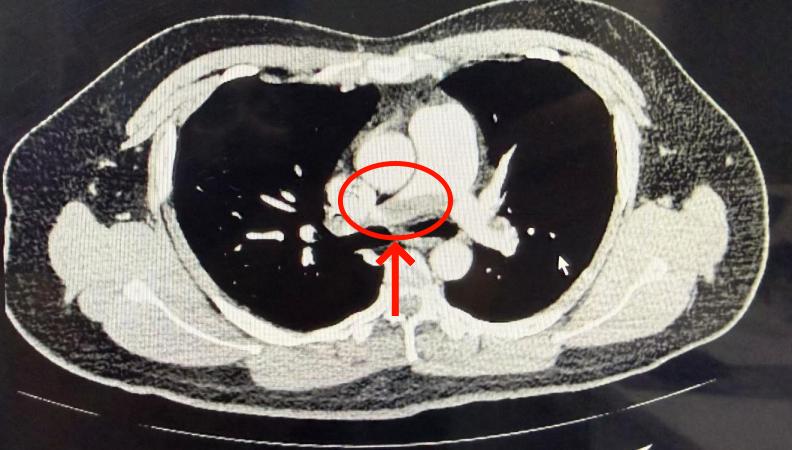

任柏沉(肺血管疾病及介入组主诊医师):肺栓塞,简单来说,就是有东西(比如血块)堵住了肺里的血管,导致肺的某些部分得不到血液供应。这会引起一系列症状,比如:喘不上气、呼吸困难、胸口痛、头晕甚至突然晕倒、咳嗽、咳血、严重时甚至休克死亡。所以,如果突然出现不明原因的呼吸困难、胸口痛或晕倒,我们都要怀疑肺栓塞的可能。这时候,医生通常会建议做一个专门的胸部增强CT检查,来帮助明确诊断。

红色箭头即为肺血栓栓子